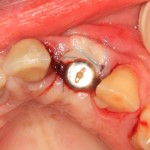

Снятие коронок, удаление вкладок

Если мы ставим задачей аккуратное и малотравматичное удаление зубов, нам необходимо избавиться от всего, что может этому помешать, а именно — от коронок и вкладок. Мы сняли коронки с помощью обычных прямых щипцов (даром, они отваливались каждые несколько месяцев), затем с помощью байонетов извлекли вкладки:

У нас отпали последние сомнения в целесообразности нашего плана лечения — при подобном состоянии корней 11, 21 зубов, их просто невозможно спасти. Следовательно решение об удалении/имплантации было правильным.

Кстати, на этом этапе можно сделать фото и показать его пациентке - как раз для того, чтобы у неё тоже не было сомнений в правильности принятых решений.